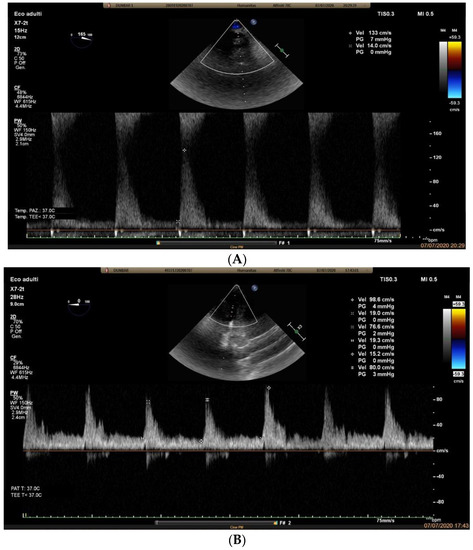

2.3. Case Report 2